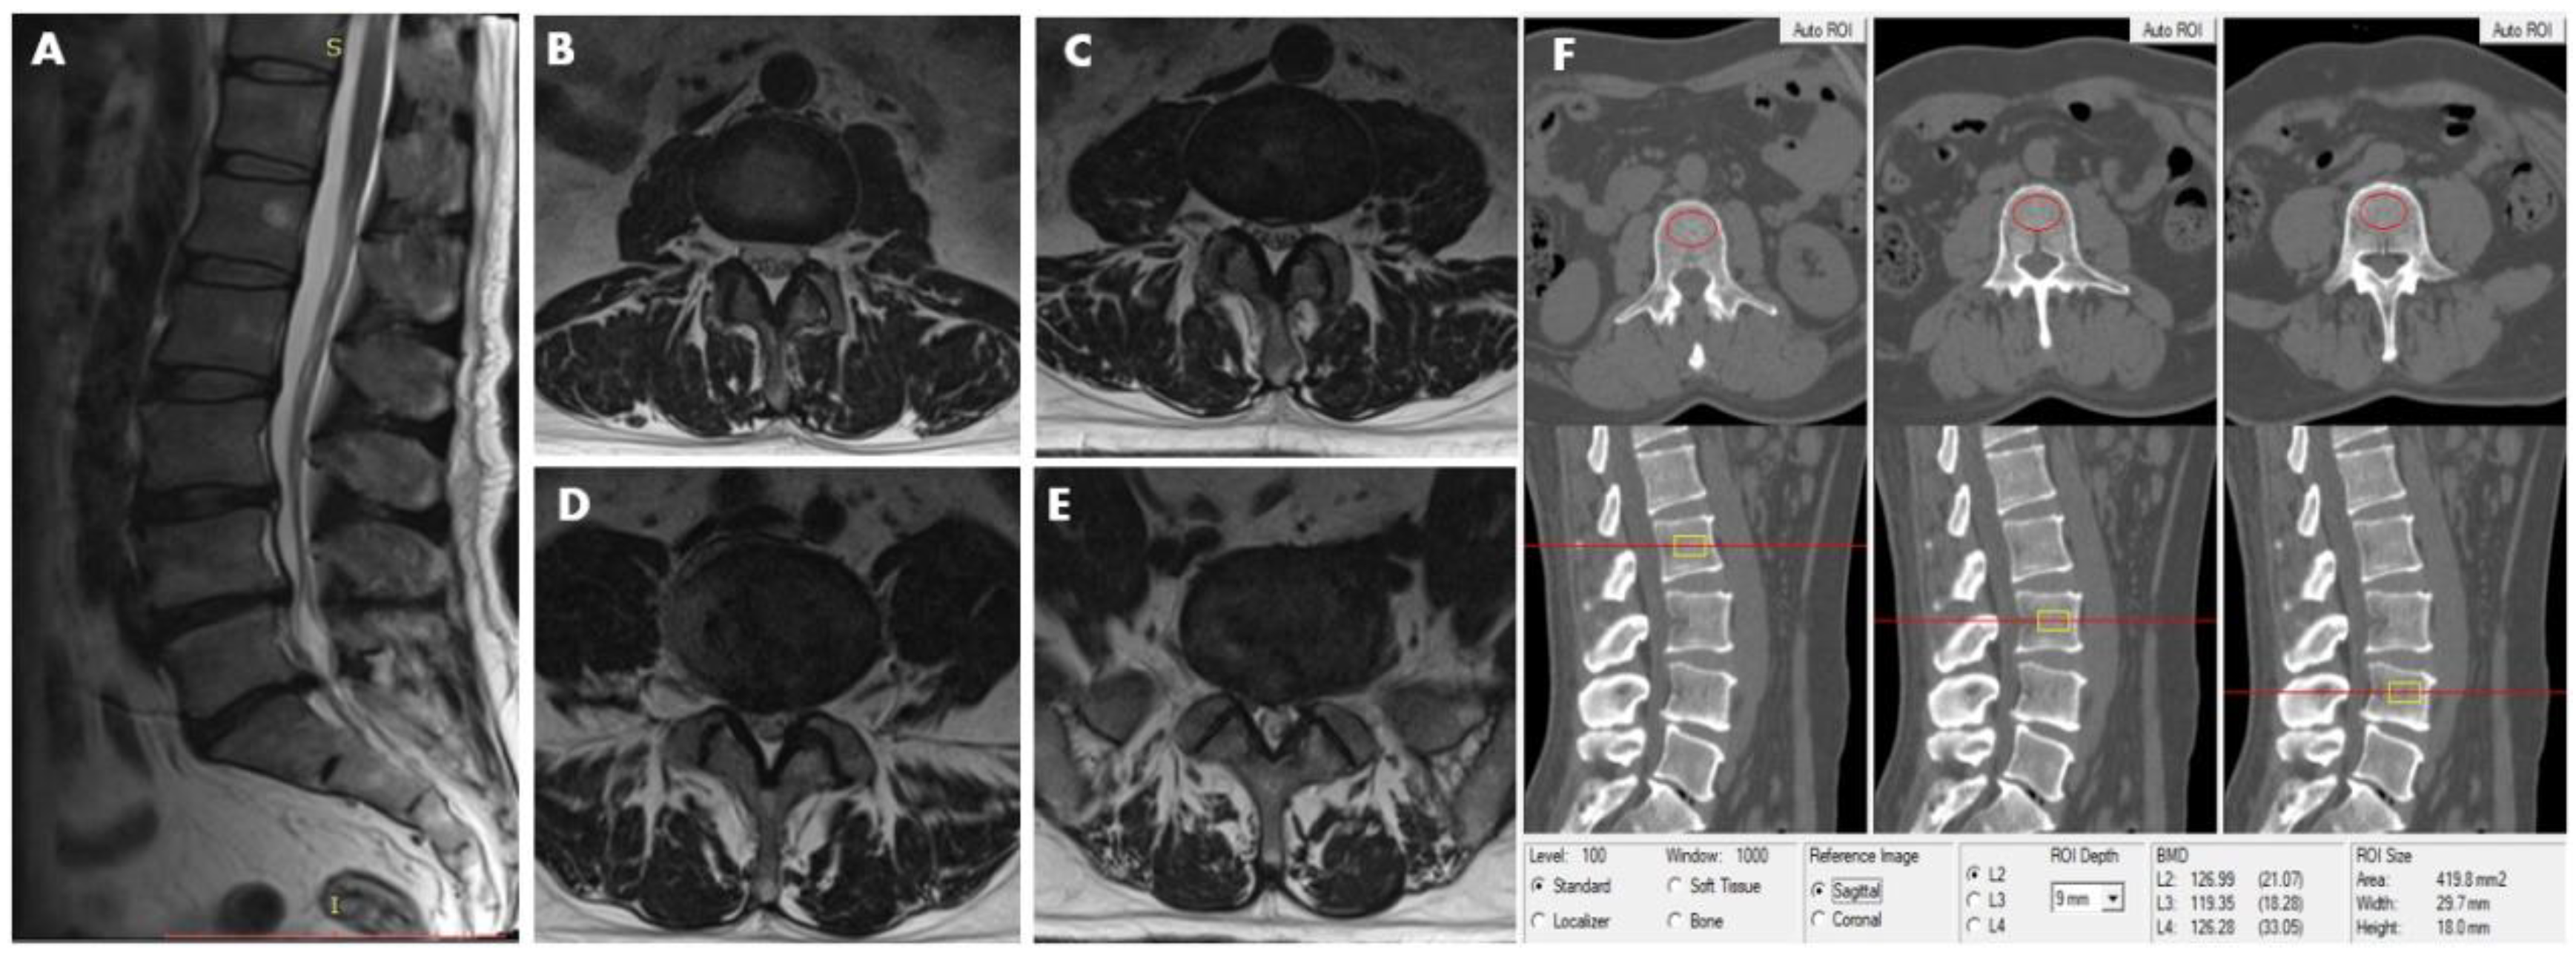

Figure 3.

This 48-year-old male participant was assigned to the LDH group and subgroup 2, simultaneously. MRI (T2-weighted image) revealed lumbar disc herniation condition from L2–3 to L5—S1disc. (A) Sagittal image revealed lumbar disk herniation in L3–4, L4–5, and L5–S1. (B) L2–3 axial image shows no abnormality in disc morphology. (C) L3–4 axial image shows focal protrusion at the central canal zone with a high-intensity zone (HIZ). (D) L4–5 axial image shows broad-based protrusion at posterolateral or dorsally, decreasing the diameter of the spinal canal and the foramen. (E) L5/S1 axial image shows asymmetric bulge companion with a focal protrusion, the right normal epidural fat layer between the two is not evident (at least the contact). (F) The measurements of L2, L3, and L4 vertebral trabecular volumetric bone mineral density (Trab.vBMD) are shown; the BMD of L2, L3, and L4 is 126.99 mg/cm3, 119.35 mg/cm3, and 126.28 mg/cm3, respectively; the average lumbar Trab.vBMD is 124.21 mg/cm3.